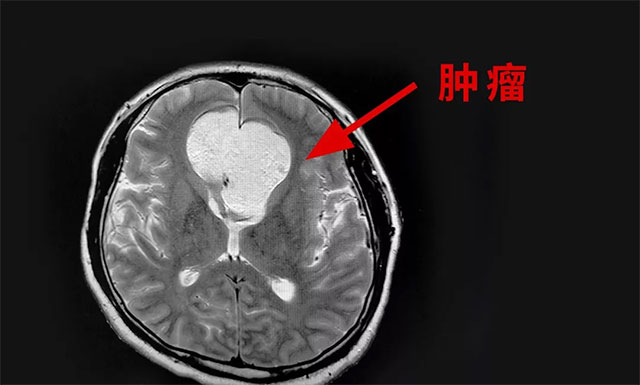

▲ 影像顯示腫瘤有拳頭大小

頭顱磁共振檢查顯示,額部(中線處)見團(tuán)狀異常信號灶,矢橫高徑約5.8*5.5*5.4cm,周圍腦實(shí)質(zhì)受壓移位,腫塊向鞍內(nèi)生長。

由潘仁龍主任、李士其教授、吳治群博士組成的專家組會診后考慮為顱內(nèi)膽脂瘤,并且患者顱內(nèi)腫瘤變性壞死破裂進(jìn)入腦室,造成了化學(xué)性腦室炎,使患者產(chǎn)生顱內(nèi)高壓癥狀(即刻腰穿,壓力高達(dá)330mmH2O),誘發(fā)癲癇發(fā)作。專家組認(rèn)為,患者病情加重,需盡快手術(shù),緩解顱內(nèi)高壓癥狀,抑制癲癇發(fā)作,盡快緩解病情,挽救患者生命。